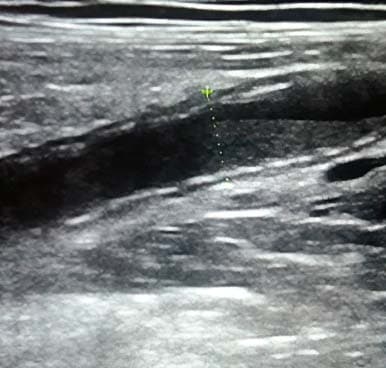

Аппендикс считается расширенным, если под действием компрессии его наружный переднезадний размер, измеренный при поперечном сканировании, более 6 мм (см. рис. 3).

Рисунок 3. Определение диаметра аппендикса.